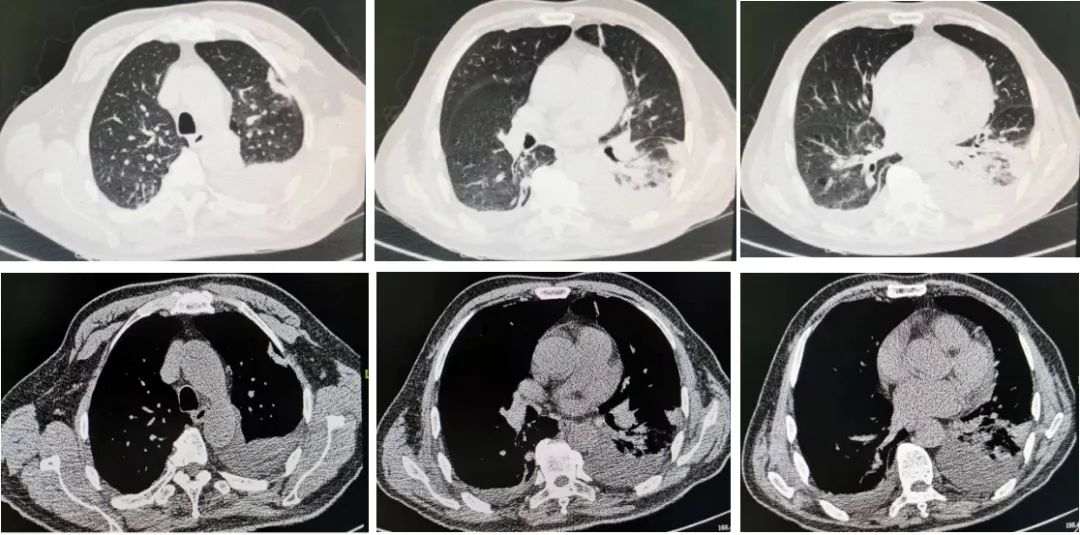

多西环素治疗2周后,患者未再出现发热症状,无头晕、乏力、呕吐等症状,一般情况良好。为了解肺部炎症吸收情况,我们复查了胸部CT(图11、图12):

图11:7月6日胸部CT。

图12:7月19日胸部CT,多西环素治疗后随访,肺炎较前明显吸收。